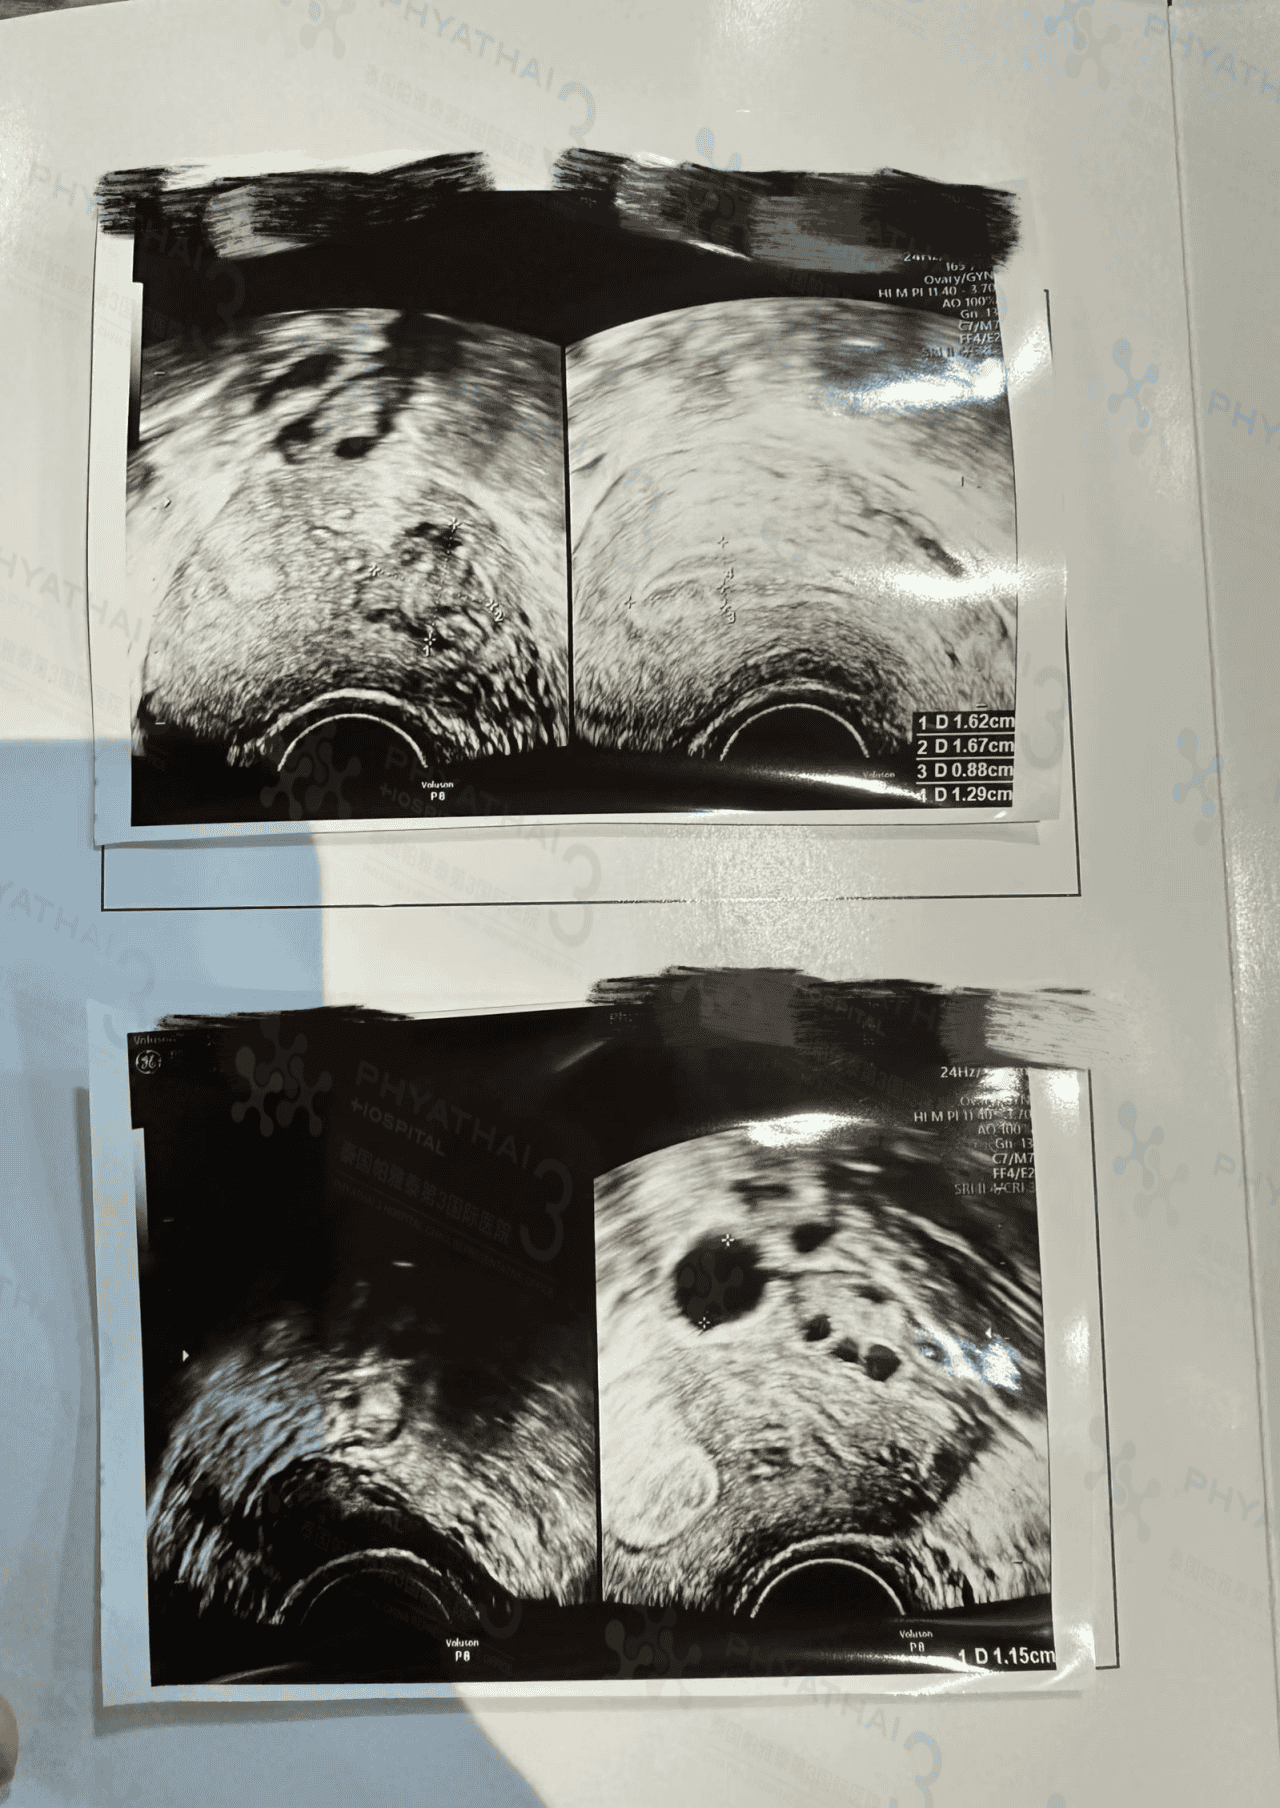

周末好啊!帕3医院的周末是人流不断,车水马龙的形象啊。今天带小姐姐移植前见诊,检查结果内膜厚度不错,宫腔有肌瘤,卵泡边边有小囊肿,但是都没有挤压到子宫,医生说对移植没有影响哦。小姐姐是移植一枚1号小粉胚胎的,医生定在4号移植啦,今天签移植前注意事项和开了调理内膜药回去继续服用,移植顺顺利利~4号见哦。